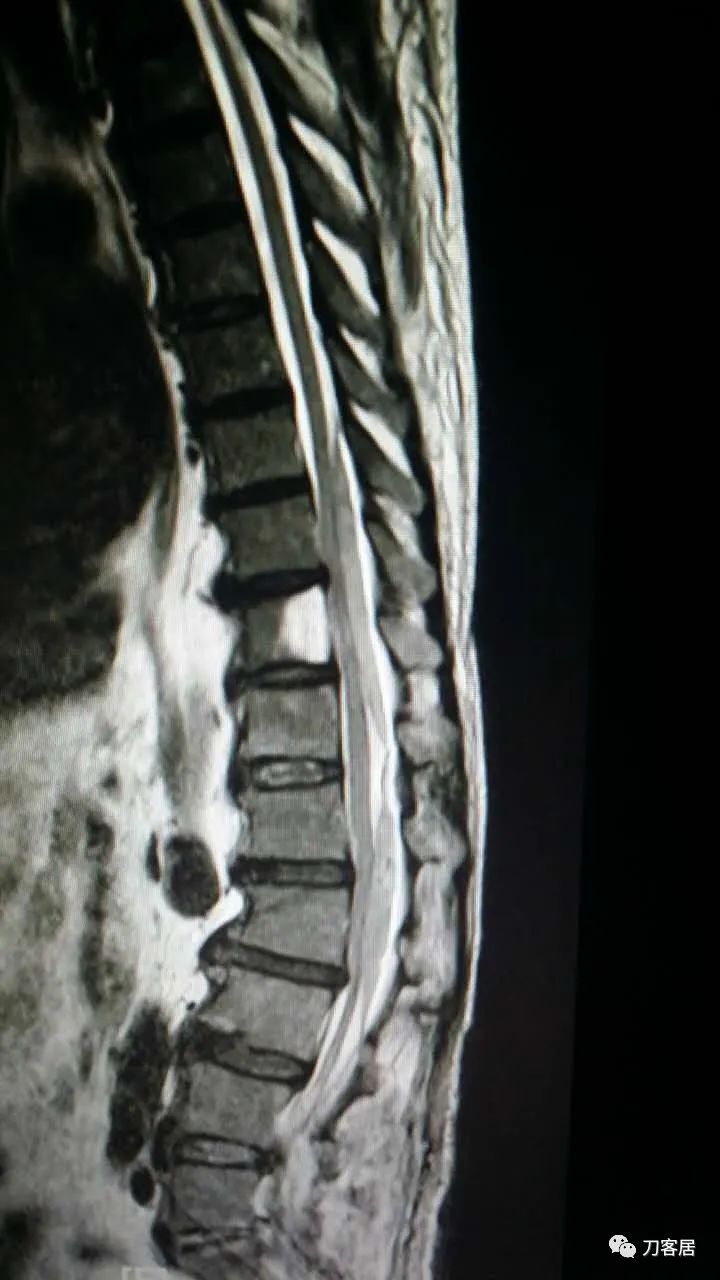

加注图23. 8月20日复查腰椎MRI,血肿占位缩小。

加注图24. 8月20日复查腰椎MRI,血肿占位缩小。

教授,早上好!这是上午刚复查的磁共振,血肿小多了。左腿还是有酸痛,这两天比刚穿刺完明显,但是肌力还是好的。

加注图25. 8月20日腰椎MRI与17日MRI对比。(此图与加注图26是一样的)

加注图26. 8月20日腰椎MRI与17日MRI对比。(此图与加注图25是一样的)

加注图27. 8月20日腰椎MRI与17日MRI对比。上面的日期清晰一些。